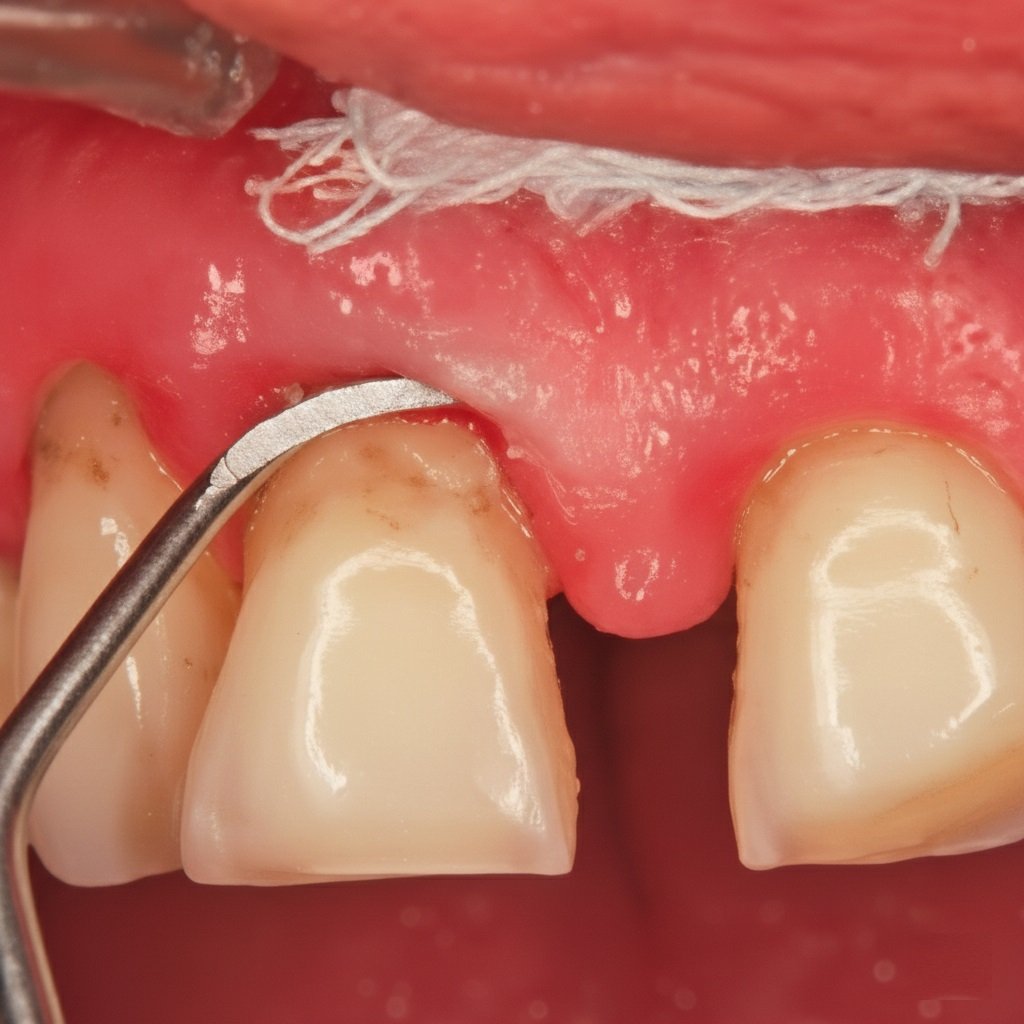

Surfaçage Radiculaire

Immédiatement après le surfaçage :

L’attache épithéliale est rompue, créant une communication directe entre le tissu conjonctif et la surface radiculaire.

Deux heures après :

On peut observer :

- De nombreuses cellules polynucléaires neutrophiles

- Une vasodilatation locale

- De l’œdème

- Des signes de nécrobiose tissulaire

À ce moment, les cellules épithéliales montrent une très faible activité prémitotique (préparation à la division).

24 heures après :

On trouve des cellules épithéliales en intense activité mitotique dans toutes les zones épithéliales résiduelles. La prolifération épithéliale est lancée.

2 jours après :

Le sillon est entièrement recouvert d’épithélium. Cette rapidité de couverture peut être problématique car elle peut empêcher la formation d’une nouvelle attache conjonctive.

4 à 5 jours après :

Une nouvelle attache épithéliale apparaît dans la partie apicale du sillon. La guérison épithéliale complète se produit en une ou deux semaines.

Important : Cependant, le tissu conjonctif n’est mature que 6 à 9 semaines après surfaçage radiculaire.

Implication clinique : C’est pourquoi il faut respecter un délai d’au moins 6 à 8 semaines entre le surfaçage et une éventuelle chirurgie parodontale, pour permettre la maturation conjonctive complète.